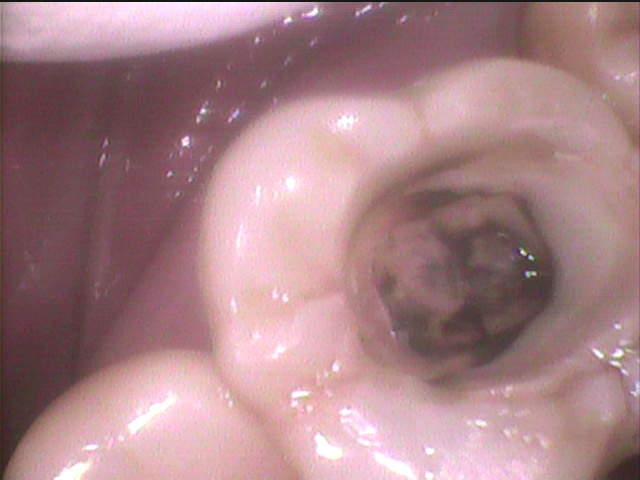

かなり除去しましたが

黒さの判定・・・おそらく過去に充填された金属が

参加されて金属イオン溶出して歯を

黒く着色していると判断。

さらに除去すると二次象牙質で

髄腔はカチカチ

限界まで虫歯を除去したのち

抗菌剤と特殊なジェルを練和して

虫歯菌に対応。